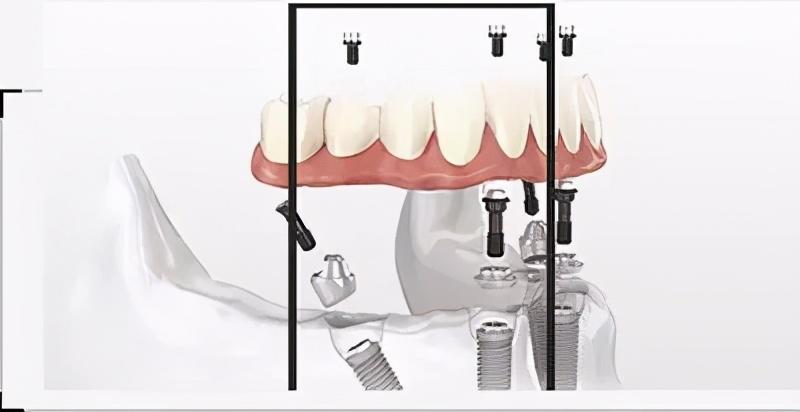

確定能手術(shù)后,才會診斷取模、制定種植牙方案。(第一次大約1個(gè)多小時(shí))然后正式開始種植牙手術(shù)。在牙槽骨上制備一個(gè)孔,植入人工種植體。將牙骨床內(nèi)嚴(yán)密縫合,大約一個(gè)星期后可以拆線(這次大概7--10天)。

注明:此植體只是模擬位置,不做確切種植位置。